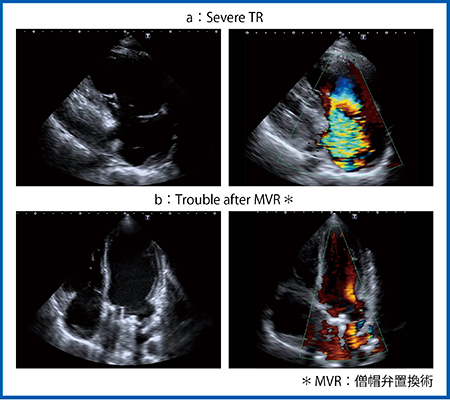

図10はカラードプラ画像であるが,三尖弁逆流(TR)が明瞭であり(図10 a右),心腔内の血流も描出されている(図10 b右)。

図10 Aplio iシリーズのカラードプラ画像